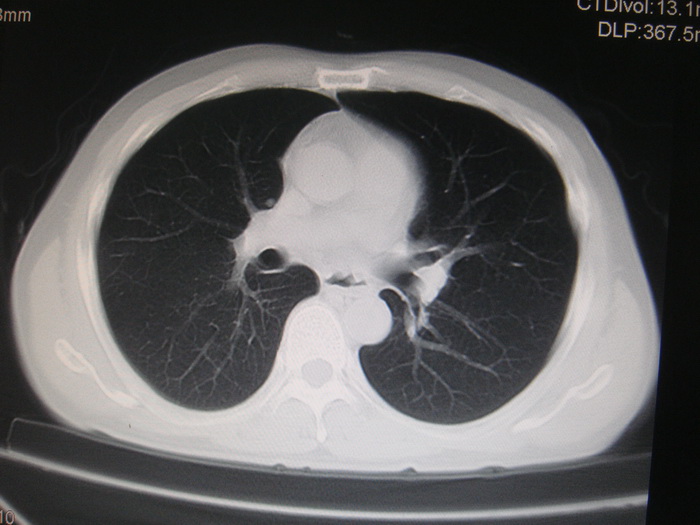

标题: CT28366:男性,45岁,偶尔发现右颈部肿块行胸部CT扫描。 [打印本页]

男性,45岁,偶尔发现右颈部肿块行胸部ct扫描。

两肺多发结节灶及纵膈淋巴结肿大考虑为转移

两肺多发性转移瘤,纵隔淋巴结转移。

两肺多发性转移瘤,纵隔淋巴结转移。食道中上段管壁似乎增厚,作相关检查。

两肺多发性转移瘤,前上纵隔淋巴结转移。